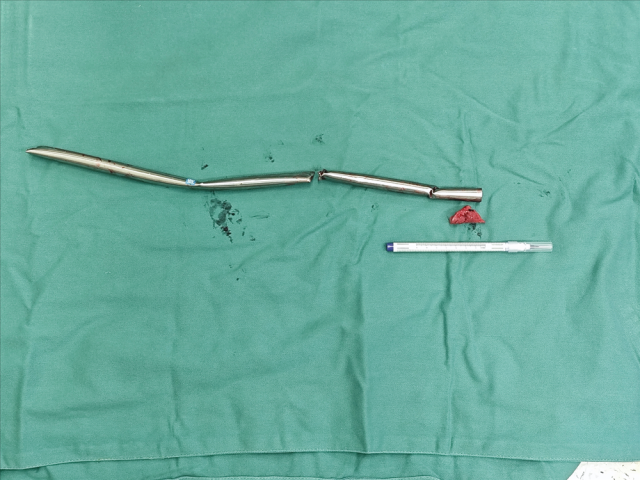

CT显示钢管刺入脊柱(箭头处)

麻醉科主治医师张海静完成麻醉后,创伤中心三线医师张骞首先进行开腹探查,检查胃肠道未见损伤,但钢管造成肝脏Ⅴ段成一个5厘米长的豁口,创面渗血。肝胆胰外科主治医师束斌上台进行肝脏修补止血。泌尿外科副主任医师肖博接力排查肾脏损伤,并为钢管拔除做重要的保护措施,游离、保护紧贴钢管的肾动脉。最后,骨科副主任医师刘华玮上台,迎来手术最关键的一步——将钢管自脊柱上取出,逐渐抽离患者体内。在事先做好的周围保护条件下,拔除过程中没有造成脏器和血管损伤,张骞医师留置引流后关腹,刘华玮及骨科团队继续完成了下肢伤口清创及骨折外架固定工作。术后患者入ICU进一步治疗,顺利拔除气管插管,下肢感觉运动正常,于术后第3天转回骨科普通病房,择期进行骨折手术。